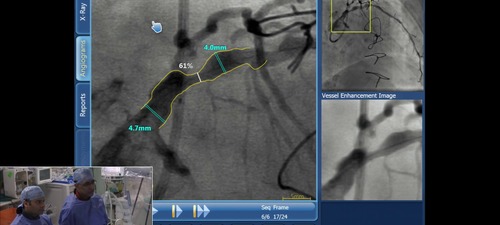

Using SyncVision to demonstrate automated coronary QCA

Demonstration showing how coronary quantitative measurements can be made in a fully automated fashion using SyncVision